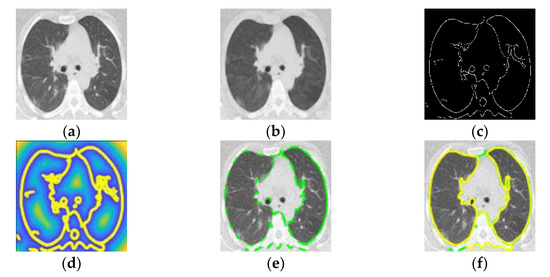

2.1. Pulmonary Parenchymal Identification by Poisson Inverse Gradient

2.2. Ground-Glass Opacity and Pulmonary Infiltrates Highlighted by Saliency Fusion